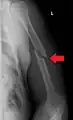

Humerus fracture

Midshaft humerus fracture with callus formation